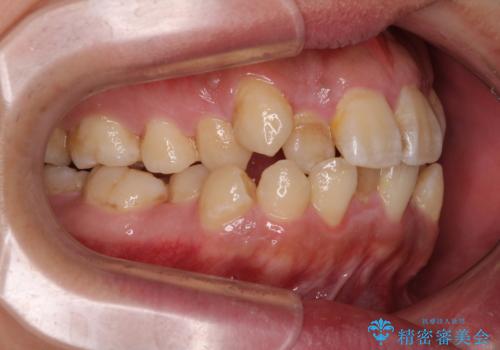

診査の結果、上下前歯に強い叢生が認められ、歯をきれいに並べるためのスペースが明らかに不足していました。

無理に歯を並べると、前歯が前方に突出するため、抜歯によるスペース確保が必要と判断しました。

上下左右の小臼歯を抜歯し、歯列を整えるためのスペースを確保

左下は第二小臼歯に根管治療歴があったため、左下のみ第二小臼歯を抜歯しアンカースクリューを併用

それ以外の部位は第一小臼歯を抜歯